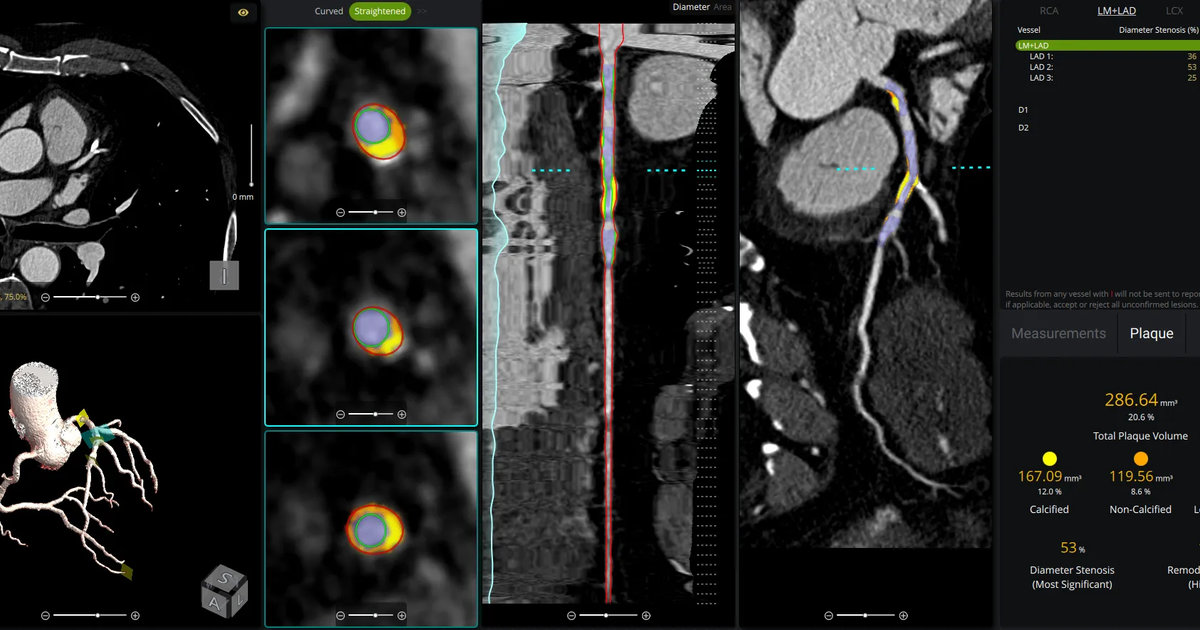

The use of AI to evaluate plaque buildup in CCTA images has been one of cardiology’s biggest ongoing trends. Implementing this software into existing workflows, however, can be a challenge. An upcoming webinar is focused on providing guidance to hospitals and cardiology practices hoping to learn more about this topic.